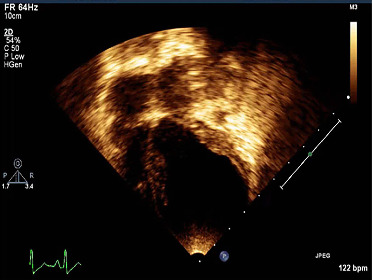

心脏结构或电生理异常可能损害心脏功能,导致心源性猝死(SCD)。严重心肌病家族的遗传筛查强调了心脏特异性基因遗传变异的作用。本研究详细介绍了1岁墨西哥儿童恶性扩张型心肌病(DCM)病例的临床和遗传特征,该病例表现为严重的左心室扩张和功能障碍,导致SCD。通过下一代测序共检测了132个基因(48个结构相关基因和84个电相关基因),以确定与对照人群相比的潜在致病突变。在计算机分析中,在一个进化上保守的肌肉合成基因ACTC1/心脏肌动蛋白(c.664G > A/p.Ala222Thr)和TTN/titin (c.33250G > A/p.Glu11084Lys)区域中,只发现了两个有害的杂合突变。进一步的系谱分析显示,该病例的父亲携带TTN突变。令人惊讶的是,ACTC1突变没有被任何一级家族成员所携带。突变蛋白的计算三维建模显示,与野生型相比,心脏肌动蛋白的静电和构象发生了变化,以及肌动蛋白致密/折叠状态稳定性的变化,这通常有助于避免机械损伤。总之,我们的研究结果表明,TTN变异共表达的ACTC1中可能存在致病性新生突变,这可能是早期发病的严重DCM和过早死亡的原因。这些结果可能会增加已知的临床致病变异,这些变异可能会严重改变心脏的结构,如果迅速检测到,就可以预防其死亡。